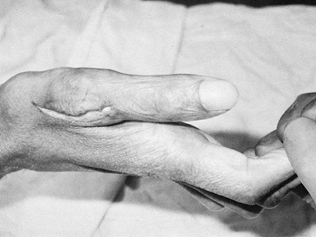

Figure 56.5. Lack of active opposition as a result of median nerve palsy.

Figure 56.6. Same patient is shown as in Figure 56.5 after superficialis transfer (palmar abduction).

Figure 56.7. The same patient is shown (opposition). -